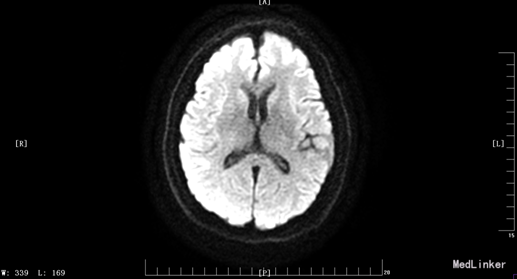

入院体检:T 36.9°C,P 87次/分,R 22次/分,BP 136/69mmHg。全身皮肤无黄染及出血点,全身浅表淋巴结未扪及肿大。双肺呼吸音清,未闻及干湿性罗音。心率87bpm,律齐,各瓣膜听诊区未闻及杂音。腹平,腹肌软,肝脾肋下未及,无压痛、反跳痛,肠鸣音正常。脊柱四肢无畸形,双下肢无水肿。神经系统:神清语晰,对答切题,记忆力、定向力、计算力正常,查体合作。双侧瞳孔等圆等大,直径约3mm,对光反射灵敏,双眼球活动自如,未见眼震。双侧额纹对称,双侧鼻唇沟对称,伸舌居中。四肢肌张力正常,左侧肢体肌力II级,指鼻试验、跟膝胫试验、闭目难立征未能配合检查。双侧腱反射对称存在,双侧巴氏征未引出。颈软,双侧克氏征、布氏征(-)。 辅助检查:生化:超敏C反应蛋白:2.6mg /l、乳酸脱氢酶(LDH):105U/L、甘油三酯(TG):2.32mmol/L、尿酸(URIC):416umol/L;同型半胱氨酸:14.3umol /l;D-二聚体定量:270ng /ml;糖化血红蛋白(HbA1c):5.1%;红细胞沉降率:3mm/h;人脂蛋白相关磷脂酶A2:378ng /ml;风湿十二项:(-); 胸部DR:主动脉硬化,双肺未见异常。心脏彩超:LVEF:66%。心内结构未见异常。 心内未见异常血流。 左室舒张功能降低。颈血管彩超:双侧颈总动脉、颈内动脉、颈外动脉、椎动脉未见异常。 双侧颈动脉、椎动脉血流速度正常。 急诊CT未见明显异常。 头颅MR:1、 双侧额叶软化灶,病灶周边少许胶质增生;2、MRA示未见明显异常。 头颅CTA:双侧颈内动脉虹吸段、双侧大脑中动脉、双侧大脑前动脉及其分支管壁尚规则,管腔通畅未见明显狭窄;右侧椎动脉颅内段管腔较左侧稍细小,余椎动脉、基底动脉及双侧大脑后动脉管腔未见明显变窄。大脑willis动脉环清晰显示,未见明显异常。 头颅CTV:大脑静脉系统上矢状窦、窦汇、横窦、乙状窦、直窦、大脑大静脉和颈内静脉管壁规则,管腔通畅未见狭窄、畸形等异常。 动态心电图示:1.窦性心动过缓;2.偶发室性早搏;3.偶发房性早搏;4.提示不完全性右束支阻滞;5.T波改变(心率快时);6.心率变异性:正常。 脑电图无异常。

患者入院时血压不高,溶栓后立即行头颅MR,未见明显病灶。但患者体征尚存在,考虑可行头颅的薄层扫描或者改变B值。另外关于栓子的来源还有疑惑,颈动脉超声没看到动脉硬化、板块,TCD结果也正常。后来再回顾病史,患者发病的过程中有感到心慌,急诊生化血钾稍低,动态心电图报有窦性心动过缓、不完全性右束支阻滞,可考虑为心源性。另患者入院时出现左手抖动、头痛症状,为刺激性症状,但MR、CTA、CTV、脑电图未见异常。也是一个疑惑的地方,希望大家给予交流指正。患者一周后出院,左侧肢体肌力几乎恢复正常。